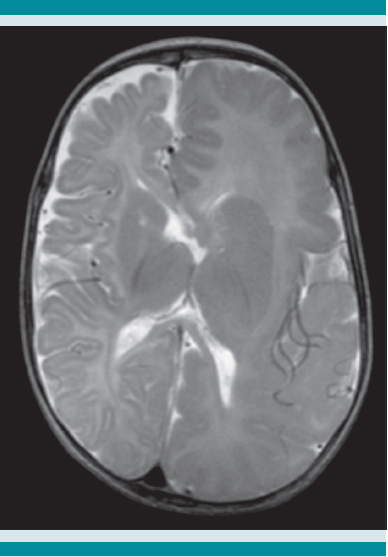

Para establecer el abordaje diagnóstico y por sospecha de síndrome neurocutáneo, por la asociación de lesiones cutáneas y manifestaciones neurológicas, se realizaron los estudios pertinentes. El electroencefalograma reportó asimetría interhemisférica por ritmo y voltaje a expensas del hemisferio izquierdo, además de paroxismos frecuentes en la región frontoparietal izquierda, sugerentes de alguna alteración estructural focal (Figura 2). La resonancia magnética mostró hemimegalencefalia izquierda y un complejo agiria-paquigiria en la región frontotemporal izquierda, compatible con los hallazgos descritos en el electroencefalograma. Figura 3

Las manifestaciones extracutáneas más frecuentes son las que afectan el sistema nervioso central (94%), sobre todo epilepsia focal de difícil control, secundaria a malformaciones corticales como: paquigiria y agiria, agenesia del cuerpo calloso y hemimegalencefalia asociada o no con hemihipertrofia corporal. Estas alteraciones estructurales pueden identificarse mediante electroencefalograma en 50% de los casos.6 Nuestro paciente tuvo malformaciones cerebrales tipo agiria-paquigiria y hemimegalencefalia izquierda, que condicionaron la epilepsia resistente al tratamiento desde los primeros días de vida.

La hemimegalencefalia es una malformación del sistema nervioso central caracterizada por el crecimiento anormal de un hemisferio cerebral, que puede aparecer de manera aislada o relacionado con el mosaicismo pigmentario tipo Ito. Esta malformación provoca manifestaciones neurológicas: epilepsia de difícil control, hemiparesia y discapacidad intelectual. La epilepsia relacionada con hemimegalencefalia suele ser resistente al tratamiento y los pacientes pueden requerir hemiesferectomía, cuyo pronóstico es sombrío, a pesar del tratamiento quirúrgico. El inicio temprano de la epilepsia y la duración de las crisis convulsivas son factores de mal pronóstico asociados con inadecuado control después de la cirugía.11 Nuestro paciente tenía ambos factores, con epilepsia de inicio en el segundo día de vida y estado parcial continuo de resistencia a los fármacos.